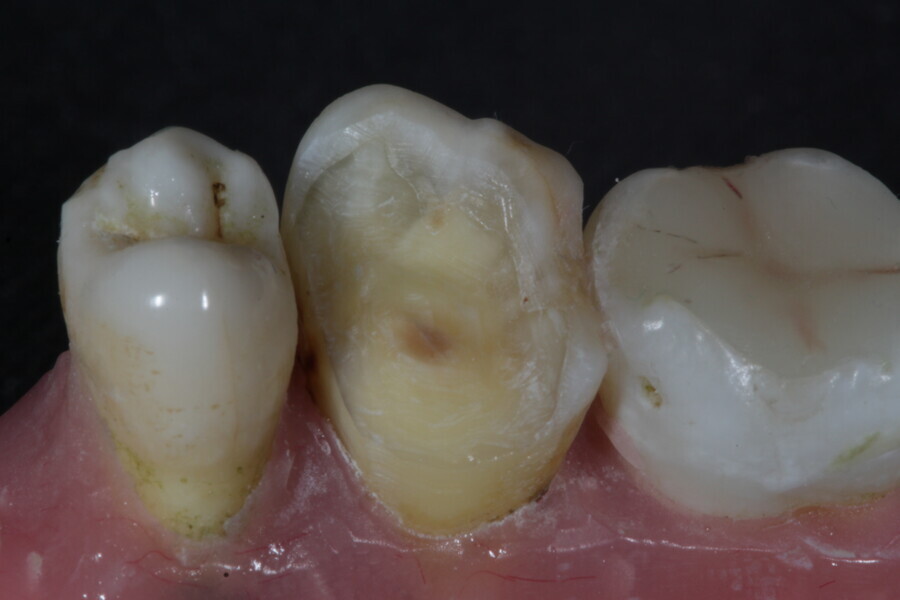

1. direct restoration using a fibre-reinforced flowable composite and membrane cube after endodontic treatment (Figs. 21–35); and

1. restoration reinforcement of a vital tooth with a fibre-reinforced flowable composite and membrane (Figs. 36–45).

Example 3—Restoration reinforcement of a vital tooth with a fibre-reinforced flowable composite and membrane.